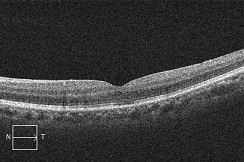

黄斑円孔の手術に関しては、?で記載しましたが、簡単におさらいすると、目の中に器械をいれて、内境界膜という網膜の表層の膜を剥離し、網膜を柔らかくします。その後、目の中に空気を入れてうつ伏せをすることで、円孔の周囲の網膜を浮力で引き寄せて、穴を閉じる。という方法です。

?正常な網膜です。中心部の赤い部分の網膜には、物を見るための視細胞が沢山集まっています。その周りの青にも、視細胞がありますが、赤に比べると数が少なくなります。緑はさらに見え方が落ちる部位です。

?黄斑円孔で、赤の部分の網膜が硝子体に引っ張られて断裂し、無くなってしまうと、視野の中心部が欠損、見たい部分が見えなくなってしまいます。